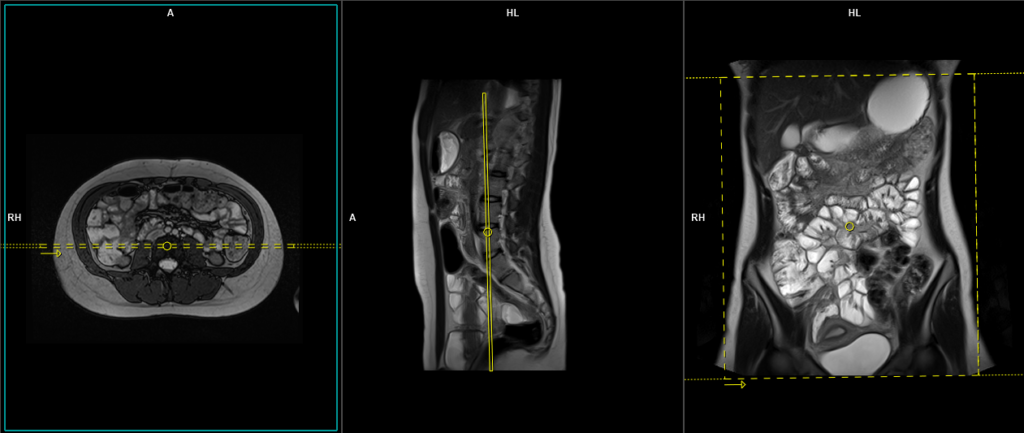

T2 HASTE 4 mm axial

Plan the axial slices on the coronal image, position the block horizontally across the abdomen as shown, and ensure that the positioning block is also checked in the other two planes. Establish an appropriate angle horizontally across the abdomen in the sagittal plane. The slices must be sufficient to cover the entire abdomen and pelvis from the stomach to the pubic symphysis. Phase oversampling can be used to avoid wrap-around artifacts. Instruct the patient to hold their breath during image acquisition.

The axial scan is performed as two separate blocks with a 20-30% slice overlap between them. The scan is performed this way to avoid any RF inhomogeneity-related artifacts by conducting the scans at the isocenter of the magnet. Use the composing function in the scanner to stitch the two blocks together.

Protocol Parameters HASTE Axial

TR 2000-2500 | TE 90-100 | FLIP 150 | NEX 1 | SLICE 4 MM | MATRIX 320X320 | FOV 400-450 | PHASE A>P | OVERSAMPLE 0% | IPAT ON |